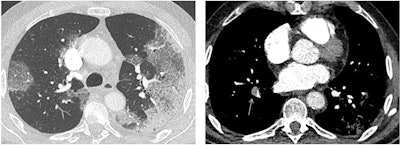

SARS-CoV-2 appears to be transmitted primarily through respiratory droplets, with a five-day median timeframe between exposure and symptoms. Thoracic CT has proven to be highly sensitive for confirming SARS-CoV-2 infection, with some studies reporting values as high as 97%, and it offers quicker results than reverse transcription polymerase chain reaction (RT-PCR) testing, according to Revel.

Revel also noted the risk of cytokine release syndrome in some patients, as well as a risk of pulmonary embolism in some patients (between 23% and 30% of those admitted to the intensive care unit with elevated D-dimer values), she told session attendees. Yet other SARS-CoV-2-infected patients develop microvascular injury syndrome involving at least the lungs and skin, which explains "why COVID-19 has clinical features distinct from typical ARDS [acute respiratory distress syndrome] with profound hypoexemia contrasting with relatively well-preserved lung mechanics," she said.